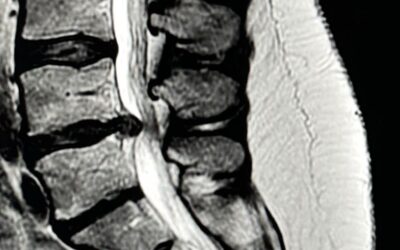

Tratamiento quirúrgico de la hernia discal lumbar: microdiscectomía vs. discectomía endoscópica

Cuando una hernia discal lumbar provoca dolor en la pierna (ciática), lo primero es intentar un tratamiento conservador: reposo relativo, medicación, fisioterapia o infiltraciones. En la mayoría de casos, estos tratamientos funcionan, pero si el dolor persiste tras...